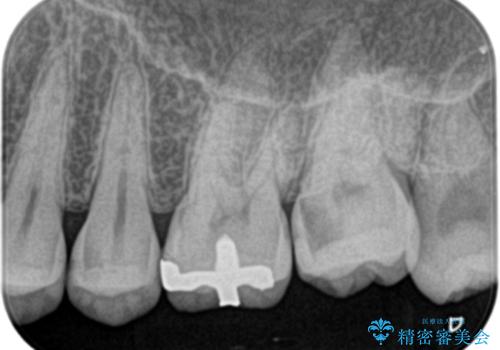

- 奥歯がズキズキ痛いことを主訴に来院されました。

治療にて歯髄は保存できないと判断したため、根管治療を行いセラミッククラウンにて修復しております。

自発痛の既往がある場合は、抜髄の適応となることが多いです。